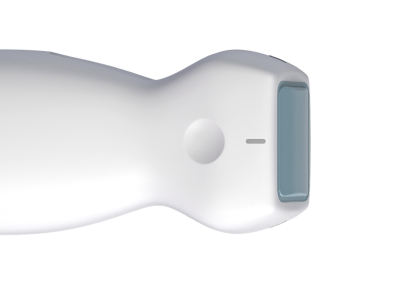

Device

Meet the device that supports the demands of the job.

Weight

300 grams

Dimensions

143 X 53 X 36 mm

Battery Life

Up to 2 hours

Waterproof and dustproof

IP67*

ERGONOMICS

3-finger grips

DURABILITY

1-meter drop tested